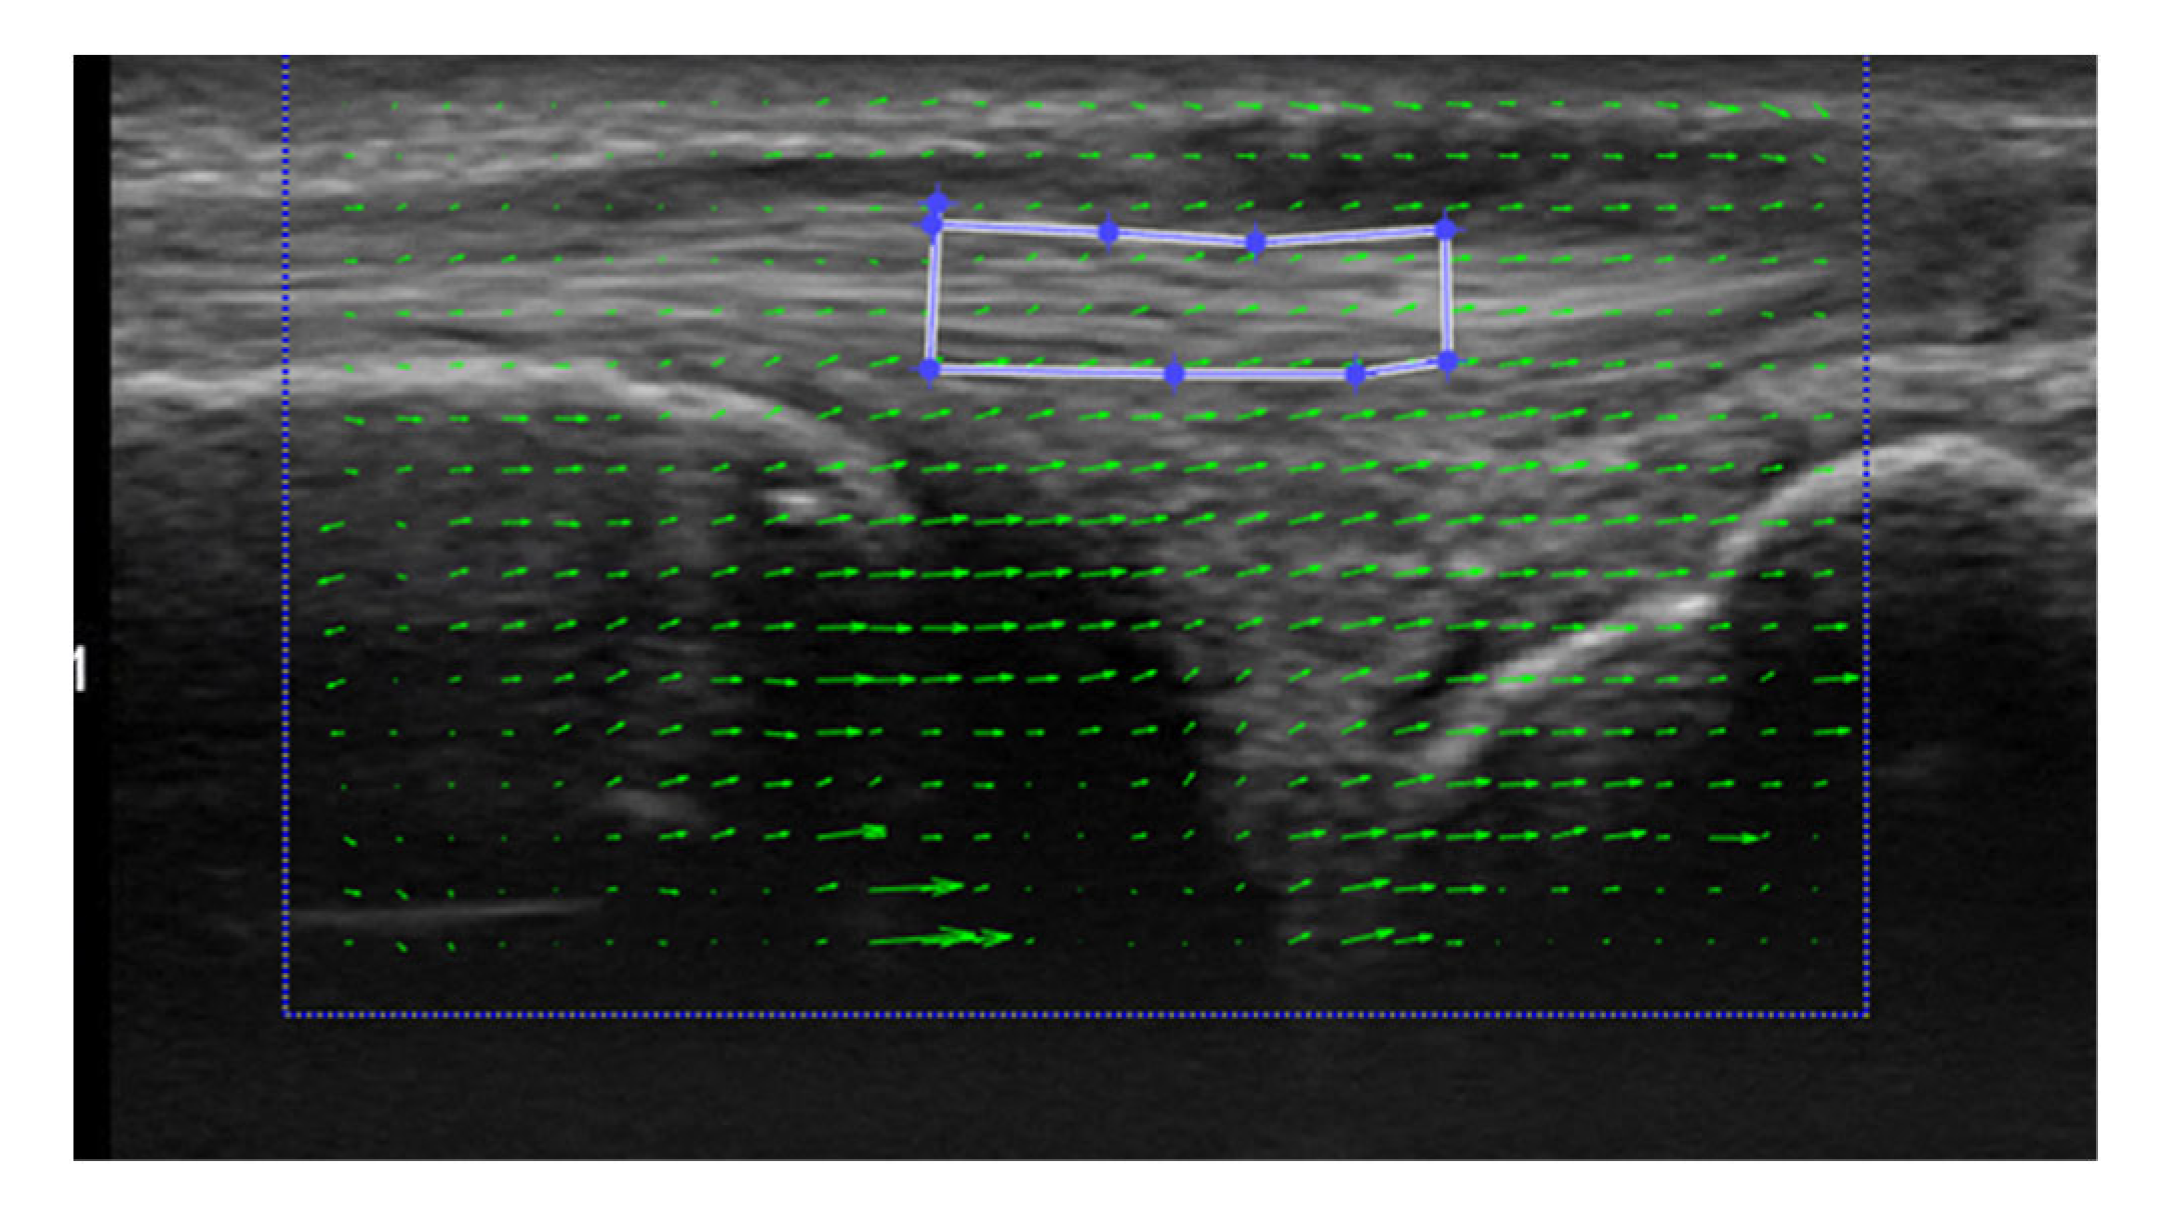

Motion Analysis of the Extensor Carpi Ulnaris in Triangular Fibrocartilage Complex Injury Using Ultrasonography Images

Tanaka, S.; Inui, A.; Mifune, Y.; Nishimoto, H.; Yoshikawa, T.; Shinohara, I.; Furukawa, T.; Kato, T.; Kusunose, M.; Kuroda, R. Motion Analysis of the Extensor Carpi Ulnaris in Triangular Fibrocartilage Complex Injury Using Ultrasonography Images. Sensors 2022, 22, 8216. https://doi.org/10.3390/s22218216